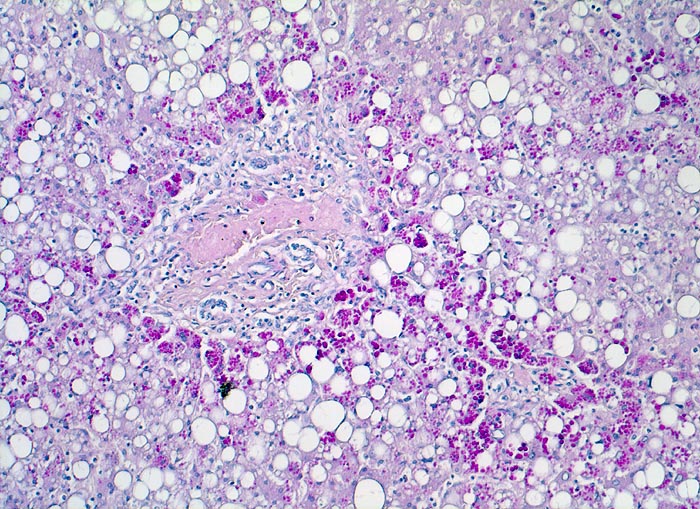

Leber bei Alpha-1-Antitrypsinmangel

Befund

Pathologischer Befund